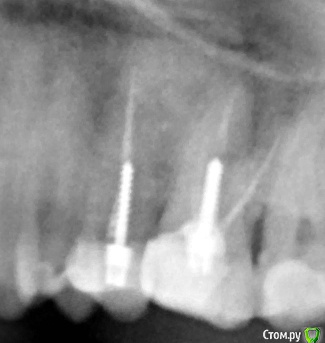

Помогите, пожалуйста, советом! Ситуация такая : В одной клинике были пролечены каналы и установлены анкерные штифты в 25,26 зубах.Зубы были восстановлены световыми пломбами с рекомендацией под коронки.С целью установки коронок обратились в другую клинику, где сначала сказали эти зубы перелечивать и ставить вкладки +коронки, но потом терапевт сказала, что при перелечивании есть большой риск того, что зубы пойдут на удаление и посоветовала накрыть коронками то, что есть..

Рисковать этими зубами не могу, поэтому пошла к ортопеду ,несмотря на дискомфорт в области этих зубов (терапевт сказала, что возможно это из-за давления пломб на дёсны..)После обточки и установки временных коронок, дискомфорт усилился и чувствую болезненные ощущения при надкусывании..Скажите, пожалуйста, по снимку( снимок до обточки) , нормально ли пролечены каналы, нет ли воспалений и как  правильнее поступить: ставить коронки на то, что есть или

необходимо всё же рисковать с перелечиванием?

К сожалению, представленный вами снимок - малоинформативен. Сделайте КТ. Решение о перелечивании принимается на основании нормального рентгенологического исследования. Симптомы, которые описываете вы, характерны для обострения хронического воспалительного процесса в кости вокруг зуба. Ни в коем случае нельзя протезировать такие зубы, без предварительного лечения.